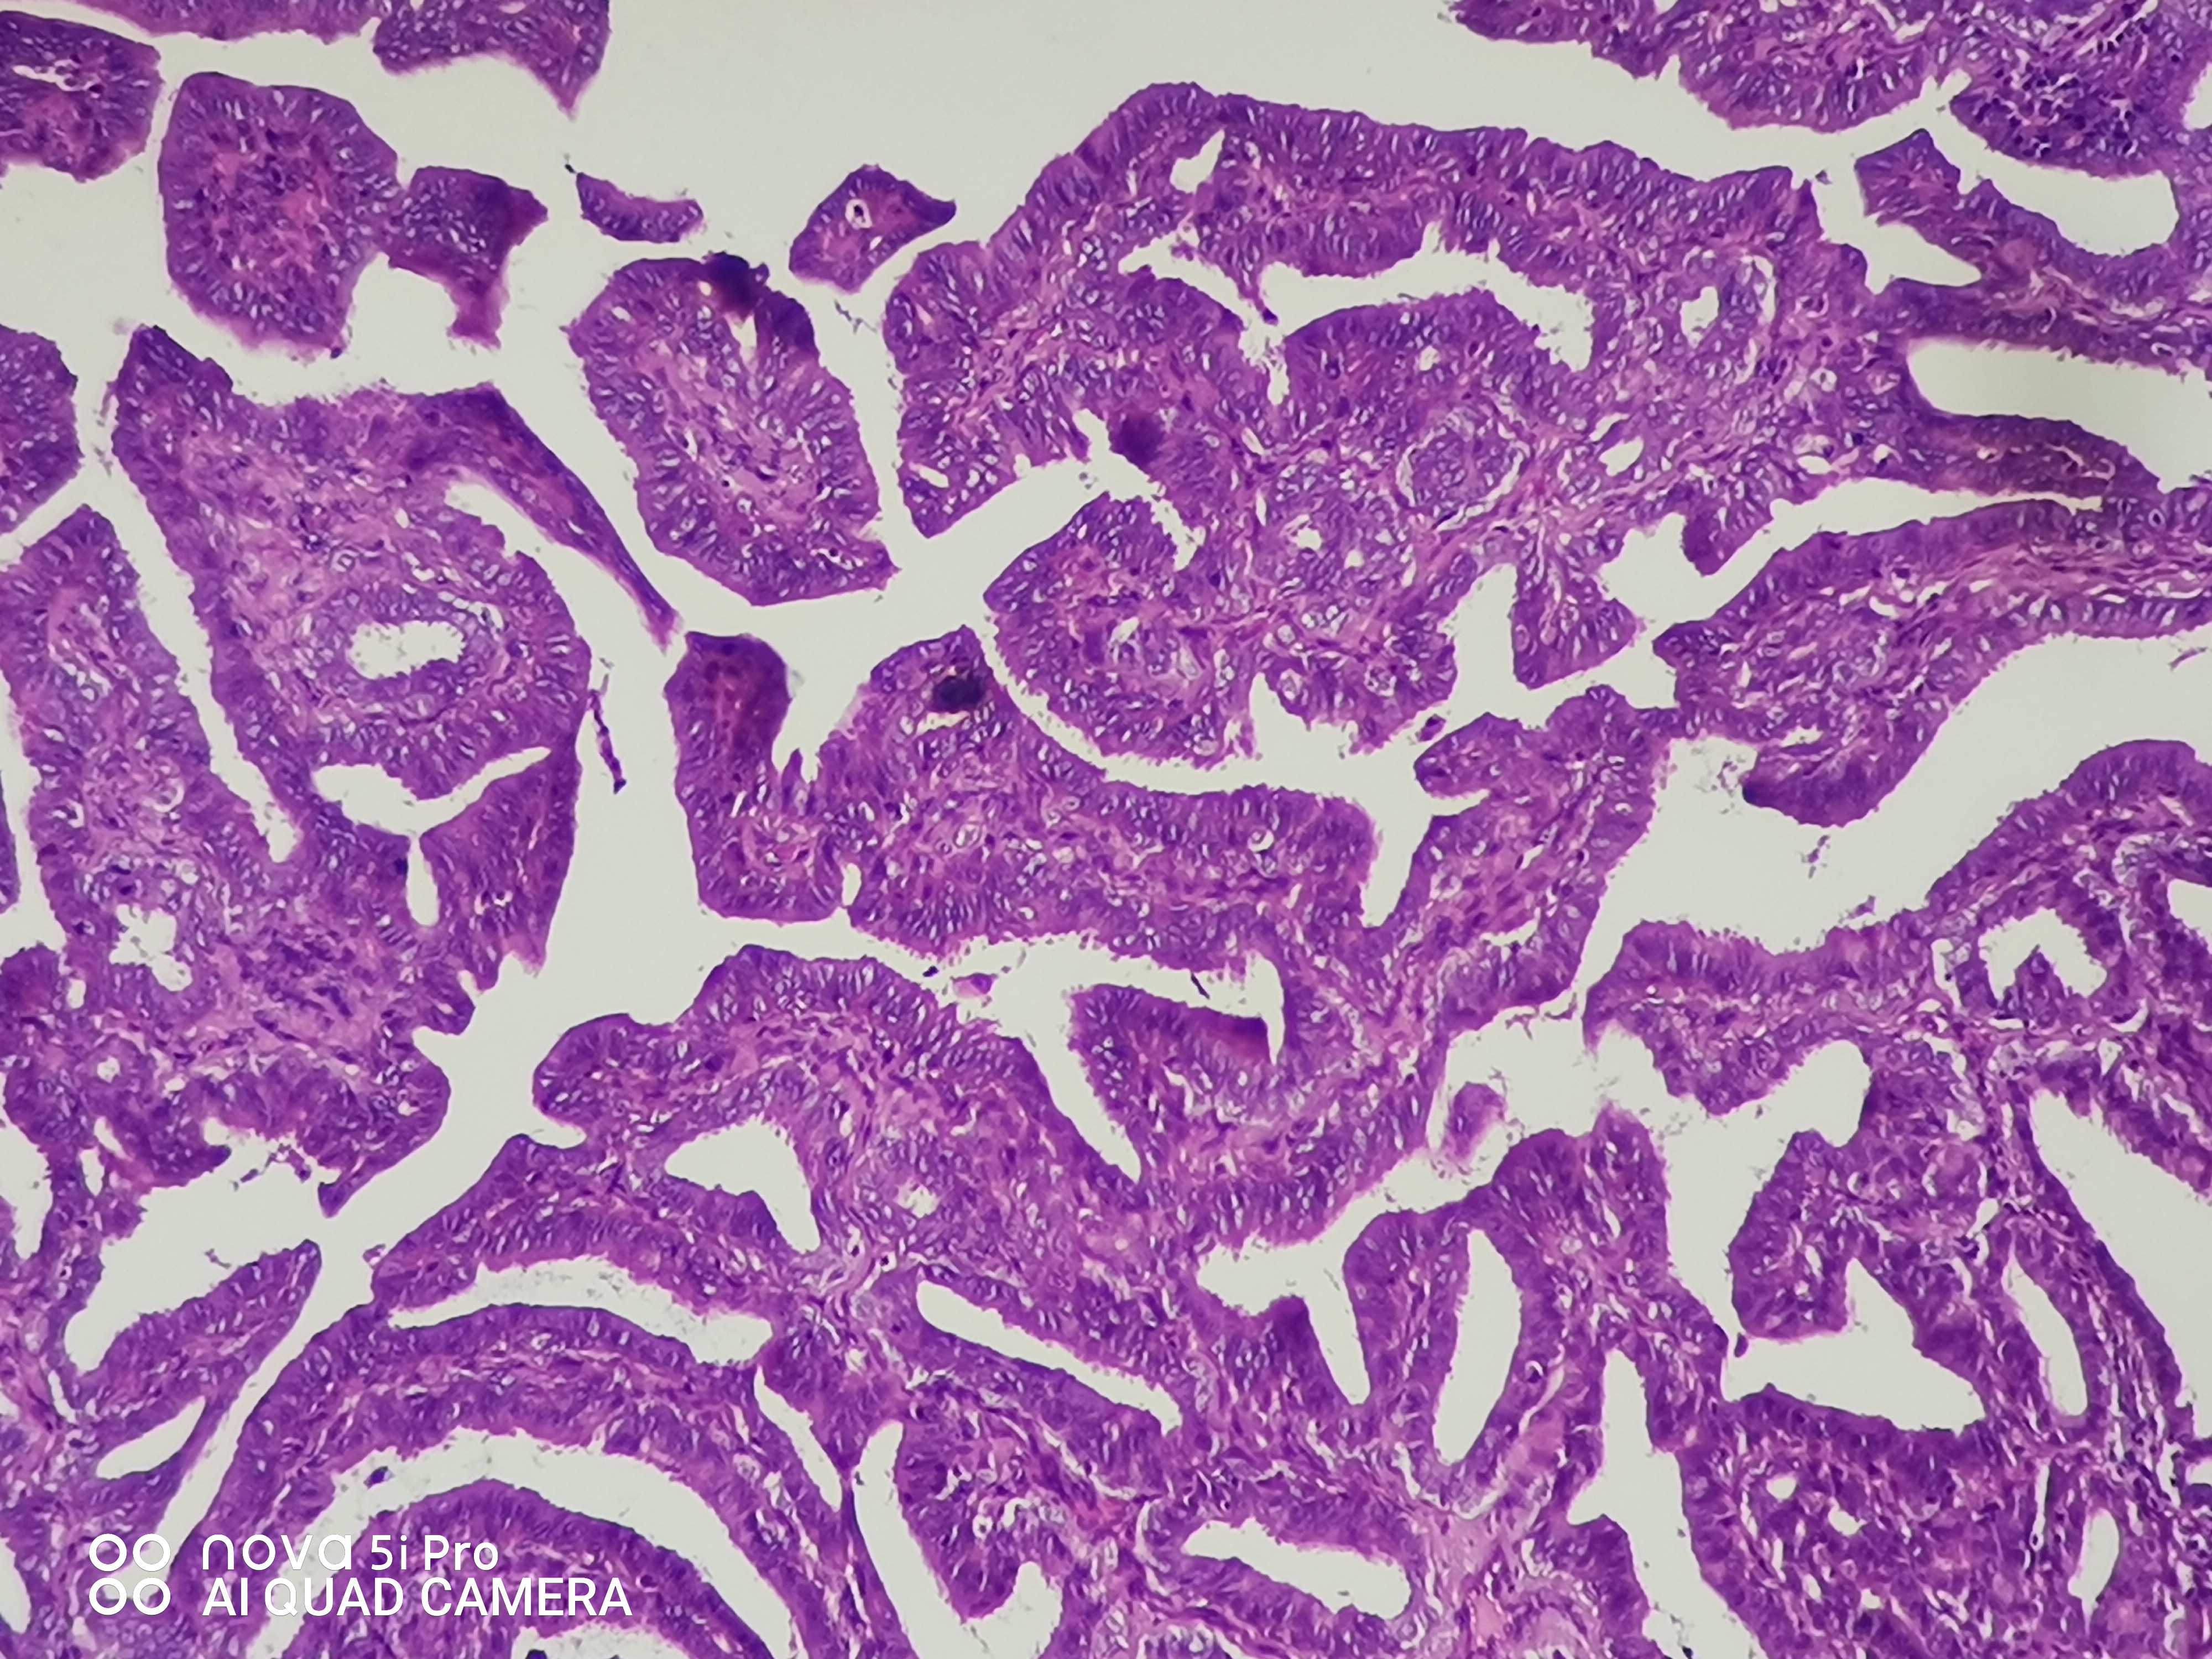

性别年龄41岁临床诊断混合痔,肛门肿块性质待查。

一般病史肛门肿块反复脱出5年,加重2月余。

标本名称肛门肿块

大体所见组织一块,大小约0.7*0.5*0.5cm,对半切开,实性灰白质中,全取。

高级别乳头状肿瘤

考虑:癌变!

乳头状汗腺瘤?

• 云子:  如果是肠上皮的话会有纤毛细胞,会有杯状细胞。杯状细胞的消失对应的是高级别肠上皮细胞病变,然而切片不支持高级别。女性外阴、肛门的这种乳头状生长模式十断头分泌现象,我更首先考虑乳头状汗腺瘤。个人意见,仅供参考!

图1可见断头式分泌,需要鉴别 汗腺肿瘤,标一下CK7.CK20.SATB-2.和P63。

这个病例的医生刚刚打电话联系我了,经省里专家远程会诊也是考虑乳头状汗腺瘤伴轻一中度非典。